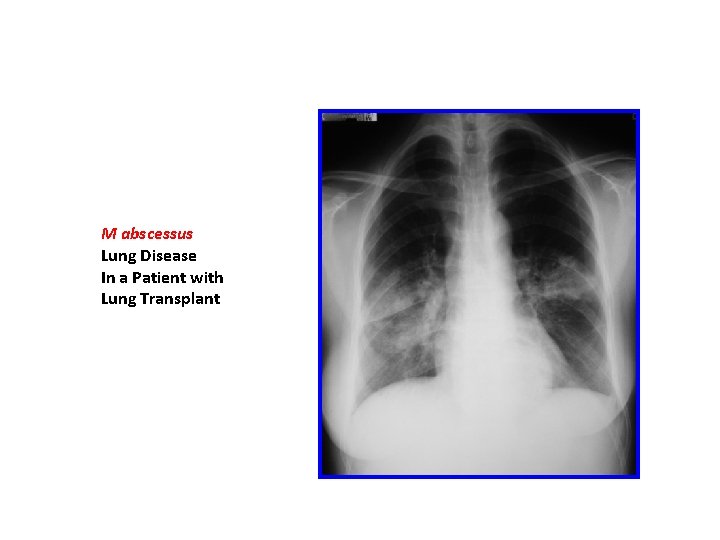

M abscessus Lung Disease In a Patient with Lung Transplant